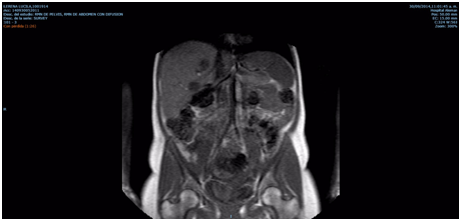

FOLFOX scheme (oxaliplatin-folinic acid-5 fluorouracil) was proposed and started. Unexpectedly, the patient presented spontaneous abortion at 20 weeks of gestational age without any apparent or evidenciable cause and nobody knows the potential relation between the main disease, the oncological treatment and the final outcome of the pregnancy. Continue with FOLFOX scheme later and the patient passed away few month later (Figure 2).

Figure 2 Liver: enlargement because multiple nodular solid images attributables to MTS.